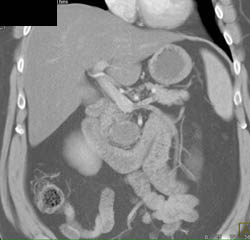

Islet Cell Carcinoma